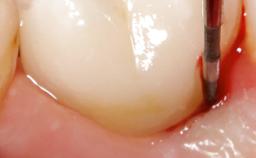

Peri-Implantitis Modified by the Presence of Submucosal Excess Cement: Reconstructive Therapy and a Ten-Year Follow-up

This case outlines the reconstructive therapy by Giovanni Salvi resulting in defect fill and inflammation-free peri-implant soft tissues at 10-year follow up. This case highlights the importance of regular monitoring of implants during supportive therapy.

A 30-year-old female patient was referred to the Department of Periodontology of the University of Bern, Switzerland, by a private dentist. Tooth 45 was congenitally missing and had been replaced with an implant three years prior to the first visit at the Department of Periodontology.